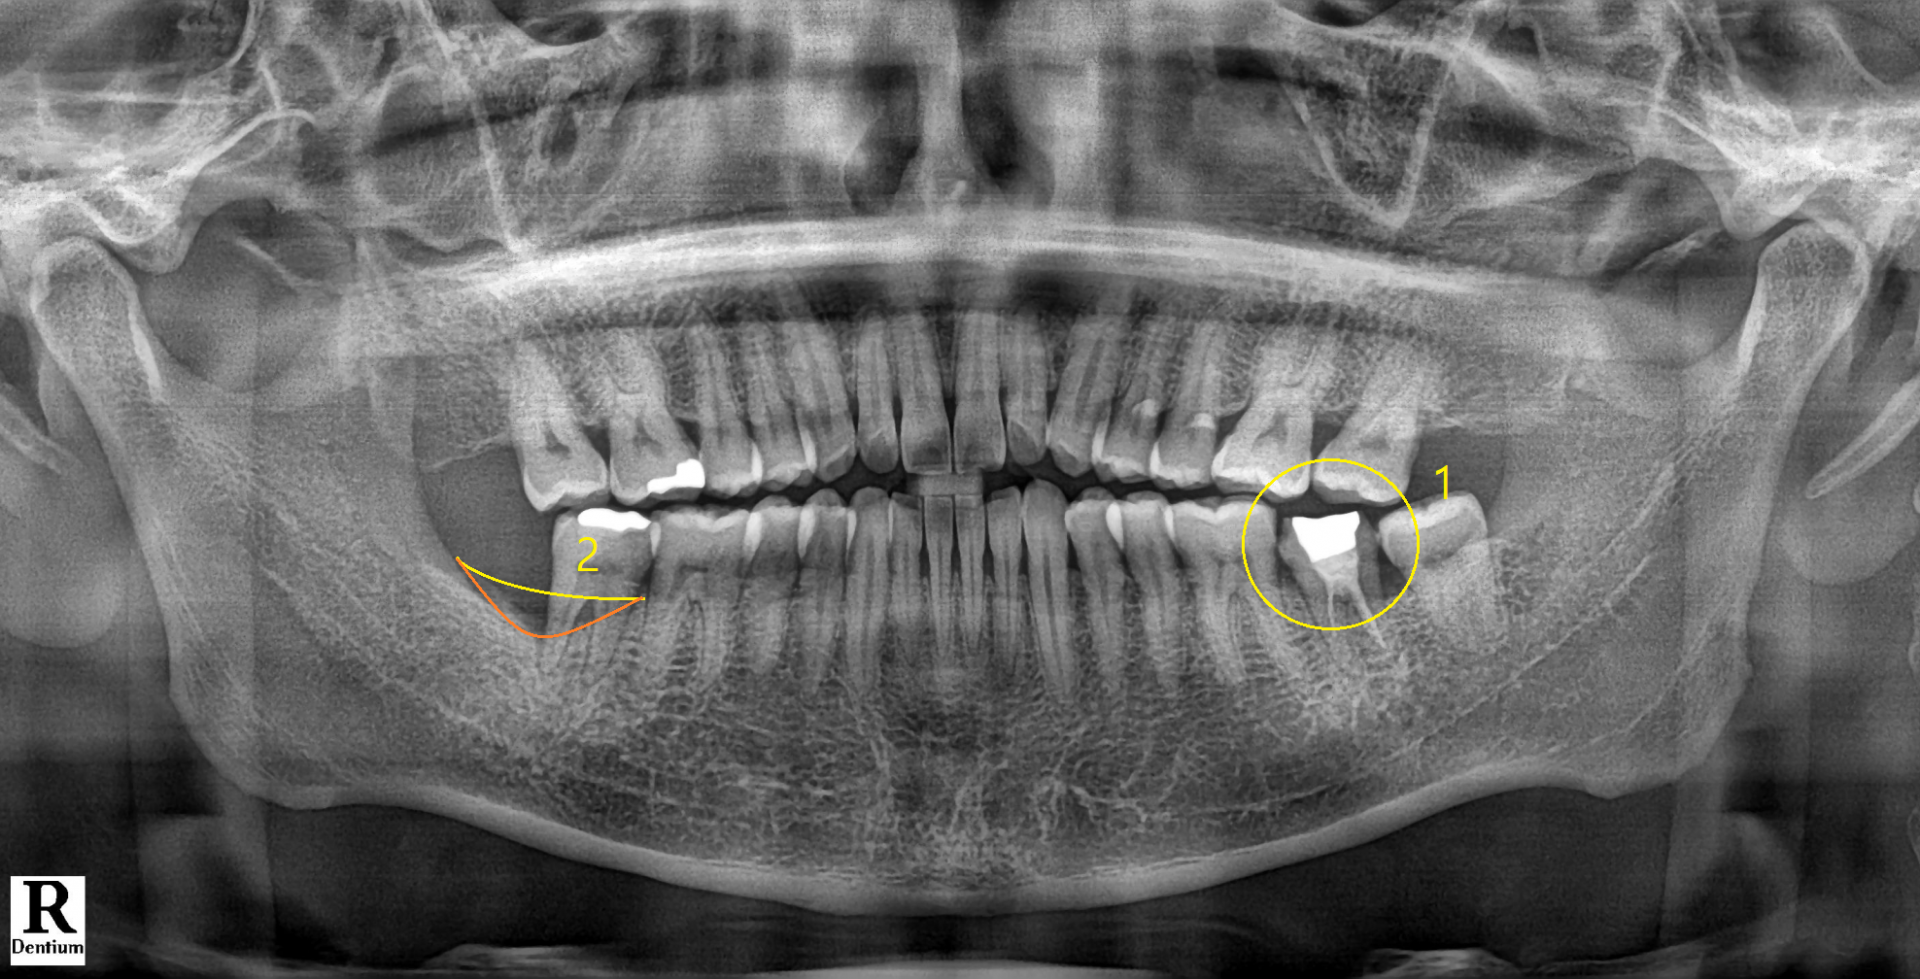

1번으로 표기된 해당 치아에 통증은 없었고, 파노라마 사진상으로도 치아 및 치주조직에 별다른 이상은 없어보였습니다.

다만 2번으로 표기된 부분은 추후 치주치료가 필요합니다.

해당 치아는 과거에 신경치료를 해둔 형태가 조금 미흡해보였습니다.

1번 근관의 경우 뿌리끝까지 흰색 재료, 흔히 Gutta percha 라고 하는 재료가 잘 채워져 있습니다.

2번 근관의 경우 뿌리끝까지 Gutta percha가 채워져 있지 않고 절반만 채워져 있는 상태입니다.